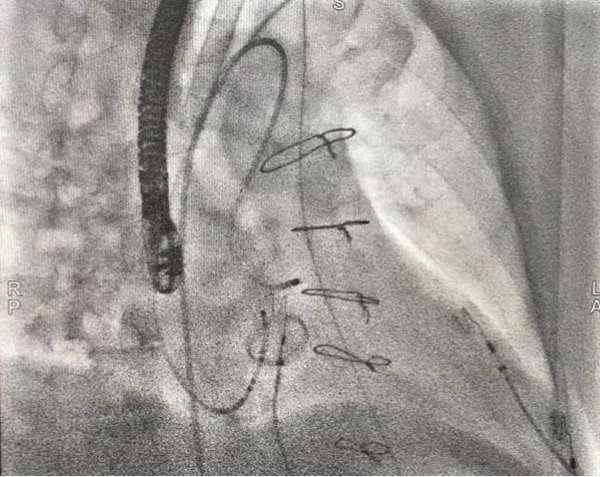

图片3_副本.png

三维显示主动脉瓣下消融靶点

患者进入手术室麻醉后,室早消失,薛荣亮主任和李伟主任对麻醉药物精确滴定,既保证有稳定的室早出现,又保证患者的麻醉效果。超声室金鑫医师迅速实施食道超声插管。心内科郑强荪主任、王洪涛医师、郝广华医师和苏丹医师随即实施手术。首先穿刺股动脉,将消融导管逆行送入主动脉窦部位,在主动脉金属瓣上谨慎操作,行激动标测,未标记到室早最早激动点。考虑患者存在主动脉瓣金属瓣,消融导管不宜直接跨瓣膜操作,遂穿刺股静脉,在食道超声指导下行房间隔穿刺,将可调弯鞘管和消融导管依次送入左房、左室,以非同平面双弯角度最终把消融电极成功送入主动脉瓣下,标记到室早最早激动点。随着放电消融的“滴滴声”,10秒后,室早即刻终止。逐步增加功率,巩固消融后,室早未再出现,大家如释重负。术后持续心电监护显示,室早一个都没有出现,彻底解决了困扰患者多年的心悸问题。

图片1_副本.png

主动脉瓣上激动标测

图片2_副本.png

主动脉瓣下激动标测和射频消融